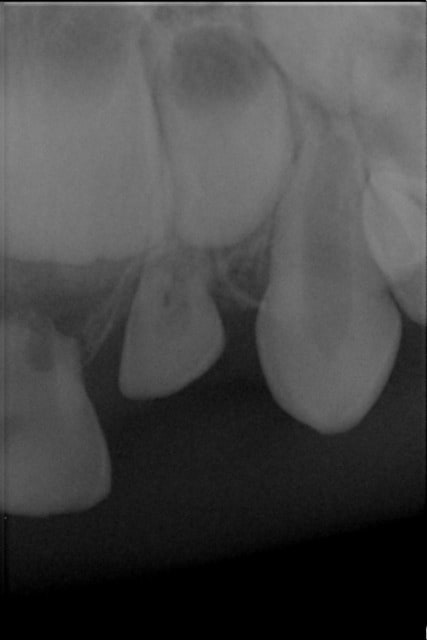

Vu le 27/07/2012 suite à une chute avec impaction de 62.

J'avais lors du rdv constaté l'ingression de 62 et demandé une surveillance à 2 mois expliquant que la dent allait redescendre.

Patient vu ce jour, la dent n'est pas redescendue, pas de rhyzalyse de la racine.

Pilpil, observe bien l'image de la racine : il y a une résorption au moins externe et peut être aussi interne.

Si la dent est accessible sans incision et enfant coopérant, je ferai l'avulsion avant que la dent devienne sous-muqueuse avec la croissance.

Sinon, je surveillerai à 6 mois puis un an : la résorption fera probablement le travail.

En effet, début de résorption!